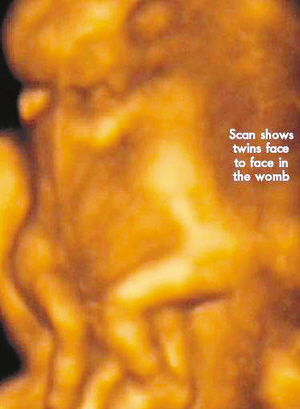

今年初,懷孕7周多的麗莎檢查發(fā)現(xiàn),懷上的竟是一對(duì)腹部緊緊相連的連體男嬰。這對(duì)連體嬰共享一只肝臟,雖然他們擁有各自的心臟,但兩顆心臟卻粘連在了一起。醫(yī)生建議麗莎立即接受流產(chǎn)手術(shù),他認(rèn)為麗莎腹中的連體嬰甚至無(wú)法活到她懷孕10周的時(shí)候。

麗莎每周都要到醫(yī)院接受醫(yī)學(xué)掃描,而她腹中的連體嬰也讓醫(yī)生感到驚訝不已,因?yàn)樗麄円呀?jīng)打破了醫(yī)生的死亡預(yù)言,一直在母親子宮中堅(jiān)強(qiáng)活到了現(xiàn)在。麗莎將于兩周內(nèi)接受剖腹產(chǎn)手術(shù)。